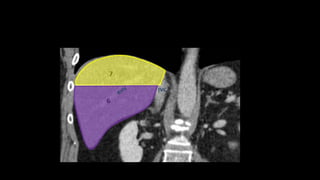

• Liver is divided into a functional

left and right liver by a main

scissurae containing the middle

hepatic vein.

• This is known as Cantlie's line.

• Cantlie's line runs from the

middle of the gallbladder fossa

anteriorly to the inferior vena

cava posteriorly.

• Right hepatic vein divides the

right lobe into anterior and

posterior segments.

• Left hepatic vein divides the left

lobe into left medial and left

lateral sections.

• The portal vein divides the liver

horizontally into upper and lower

segments.

• There are eight liver segments.

• Segment IV is divided into segment IVa and IVb according to Bismuth.

• The numbering of the segments is in a clockwise manner.

• Segment I (the caudate lobe) is located posteriorly.

• It is not visible on a frontal view.